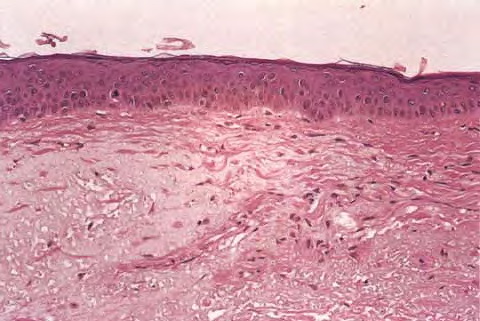

Oxidative stress upregulates the level of stress regulatory proteins, one of which is nuclear factor κB, a transcription factor that induces the expression of pro-inflammatory cytokines like interleukin (IL)-1 and IL-6, vascular endothelial growth factor (VEGF), and tumor necrosis factor (TNF)-α. These proteins are involved in immunoregulation and cell survival stimulate the expression of matrix-degrading metalloproteins,25 and are believed to play a central role in the aging process. Oxidative damage also affects telomeres. A recent hypothesis suggests a common cellular signaling pathway activated by DNA damage and involving the terminal portion of the telomeres. The terminal portion of the 3′ telomeric strand extends beyond the complementary 5′ strand (Fig. 108-1B), leaving a single stranded G-rich overhang. It is suggested that during both telomere shortening and repair of telomere damage, such as that encountered by oxidative stress, the normal loop structure at the end of telomeres is disrupted, exposing the 3′ overhang that under baseline conditions is “buried” in the loop structure. Exposure of the TTAGGG tandem repeat sequence then appears to activate p53 and to stimulate p53-dependent responses known to include proliferative senescence and apoptosis. Thus, the intrinsic component of skin aging involves progressive oxidative stress and telomere signaling as telomeres shorten during serial cell division and in response to oxidative DNA damage. EPIDERMIS The most striking and consistent histologic change is flattening of the dermal-epidermal junction with effacement of both the dermal papillae and epidermal rete pegs. This results in a considerably smaller surface between the epidermis and dermis and presumably less communication and nutrient transfer. Dermal-epidermal separation has been demonstrated to occur more readily in old skin, undoubtedly explaining the propensity of the elderly to torn skin and superficial abrasions after minor trauma. There is an age-associated epidermal thinning of 10 percent to 50 percent between the ages of 30 and 80 years. Variability in epidermal thickness and individual keratinocyte size increases, including those of the basal layer. Evidence suggests that epidermal keratinocytes senesce, and senescent cells are more resistant to apoptosis. Such keratinocytes are therefore more likely to accumulate mutations, increasing their risk for malignant transformation. Studies also show loss of epidermal stem cell population in aged skin as determined by the loss of cells expressing CD71 (transferrin receptor) and α6 integrin, accepted markers for keratinocyte stem cells.37 At the electron microscopic level, sun-protected old skin is characterized by some widening of inter-keratinocyte spaces, by reduplication of the lamina densa and anchoring fibril complex in the basement membrane zone, and by loss of the numerous microvillous projections of basal cell cytoplasm into the dermis.36 Average thickness and degree of compaction of the stratum corneum appear constant with increasing age, although individual corneocytes become larger. The skin surface pattern, a patchwork of fine lines possibly determined by papillary dermal architecture, reveals slight age-associated loss of regularity. Age effects on percutaneous absorption depend in part on drug structure, with hydrophilic substances such as hydrocortisone and benzoic acid being less well absorbed through the skin of old versus young individuals but with hydrophobic substances such as testosterone and estradiol being equally well absorbed. Of perhaps greater clinical importance, aging markedly delays the recovery of barrier function in damaged stratum corneum, apparently because of slow replacement of neutral lipids, leading to decreased amount of lipids in the newly formed lamellar bodies.39 Lipid synthesis and activities of enzymes required to generate stratum corneum lipids decrease with age possibly because of aberrations in elements that regulate enzyme transcription, or abnormal autocrine/paracrine signaling.